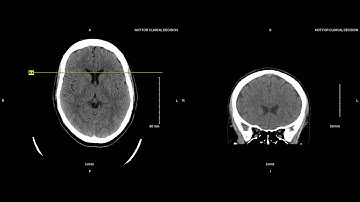

Unremarkable Non-Contrast CT Axial Bone Window-Example 3